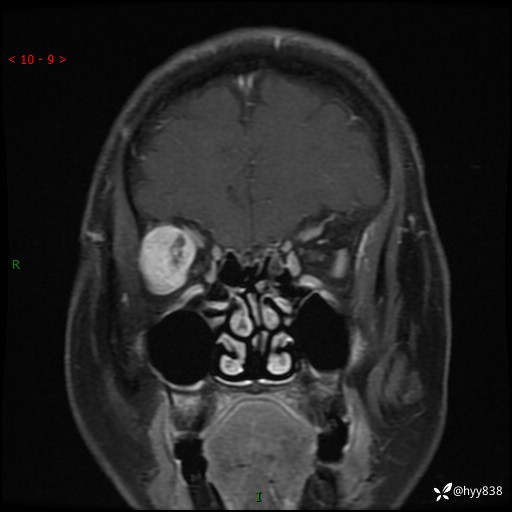

老年女性,右眼球突出1月。说说鉴别诊断,看谁第一个秒---(有结果)

主诉:发现右眼球突出1月余

简要病史:患者于1月前无明显诱因发现右眼球突出,偶感磨痛、眼胀,无视力下降,无头痛,恶心呕吐等不适。10天前就诊于当地县人民医院就诊,完善头颅ct检查,诊断为右侧眼眶肿物,建议患者上级医院进一步治疗,患者因个人原因拒绝。拟行手术,来我院就诊,门诊行相关检查后以“右眼眼眶肿物”收入院。 患病以来,患者精神饮食睡眠尚可,大小便如常、体重无明显改变。

辅助检查:MRI

临床诊断:眼眶肿物

眼眶MRI平扫+增强